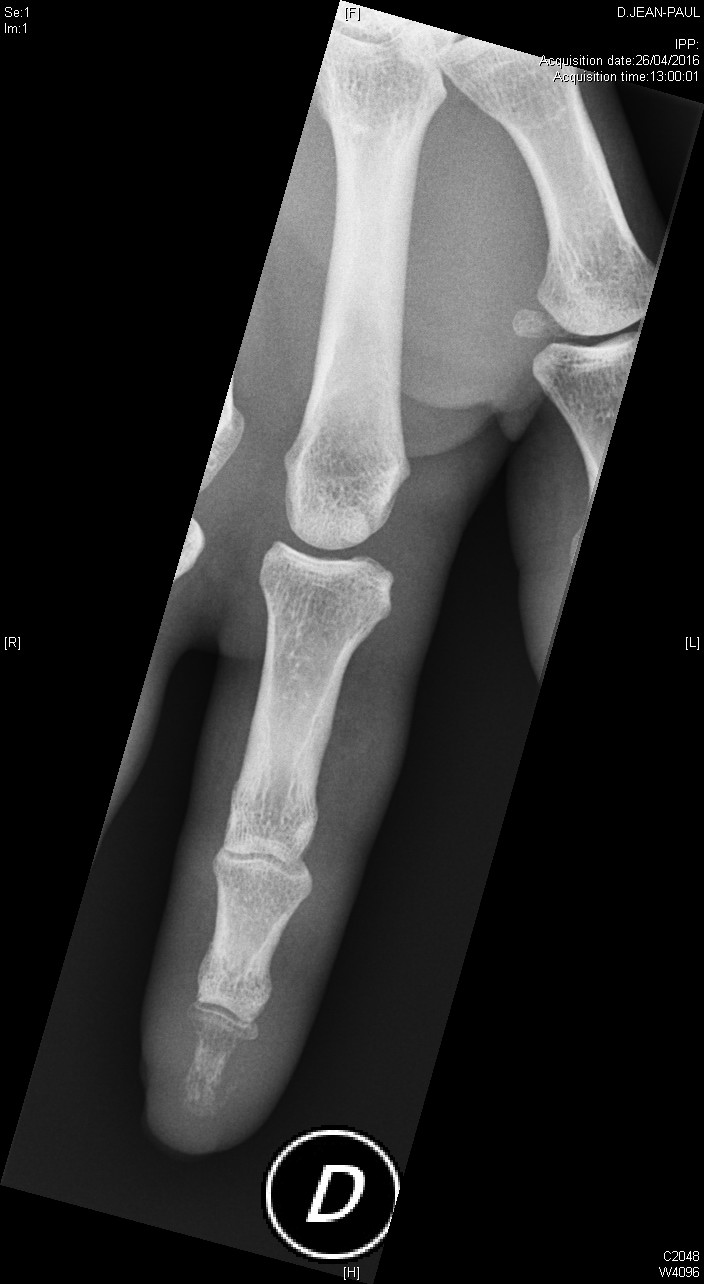

Ostéite de la phalangette

Polyarthrite rhumatoïde débutante, d'emblée érosive

polyarthrite rhumatoïde érosive avec signe de Freiberg radiographique au poignet

Polyarthrite rhumatoïde séropositive, sévèrement érosive aux pieds